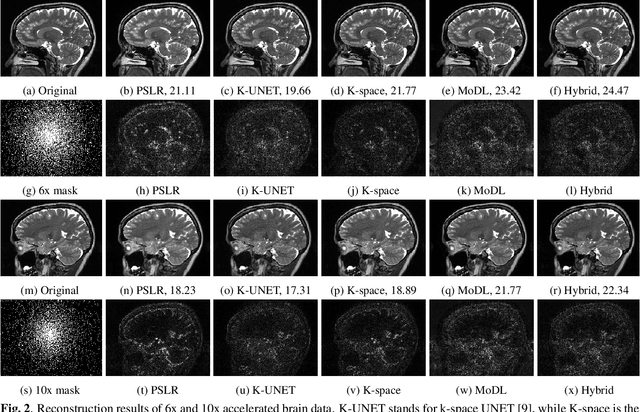

Abstract:We introduce a fast model based deep learning approach for calibrationless parallel MRI reconstruction. The proposed scheme is a non-linear generalization of structured low rank (SLR) methods that self learn linear annihilation filters from the same subject. It pre-learns non-linear annihilation relations in the Fourier domain from exemplar data. The pre-learning strategy significantly reduces the computational complexity, making the proposed scheme three orders of magnitude faster than SLR schemes. The proposed framework also allows the use of a complementary spatial domain prior; the hybrid regularization scheme offers improved performance over calibrated image domain MoDL approach. The calibrationless strategy minimizes potential mismatches between calibration data and the main scan, while eliminating the need for a fully sampled calibration region.

Abstract:Structured low-rank (SLR) algorithms are emerging as powerful image reconstruction approaches because they can capitalize on several signal properties, which conventional image-based approaches have difficulty in exploiting. The main challenge with this scheme that self learns an annihilation convolutional filterbank from the undersampled data is its high computational complexity. We introduce a deep-learning approach to quite significantly reduce the computational complexity of SLR schemes. Specifically, we pre-learn a CNN-based annihilation filterbank from exemplar data, which is used as a prior in a model-based reconstruction scheme. The CNN parameters are learned in an end-to-end fashion by un-rolling the iterative algorithm. The main difference of the proposed scheme with current model-based deep learning strategies is the learning of non-linear annihilation relations in Fourier space using a modelbased framework. The experimental comparisons show that the proposed scheme can offer similar performance as SLR schemes in the calibrationless parallel MRI setting, while reducing the run-time by around three orders of magnitude. We also combine the proposed scheme with image domain priors, which are complementary, thus further improving the performance over SLR schemes.

Abstract:We introduce a model based off-the-grid image reconstruction algorithm using deep learned priors. The main difference of the proposed scheme with current deep learning strategies is the learning of non-linear annihilation relations in Fourier space. We rely on a model based framework, which allows us to use a significantly smaller deep network, compared to direct approaches that also learn how to invert the forward model. Preliminary comparisons against image domain MoDL approach demonstrates the potential of the off-the-grid formulation. The main benefit of the proposed scheme compared to structured low-rank methods is the quite significant reduction in computational complexity.